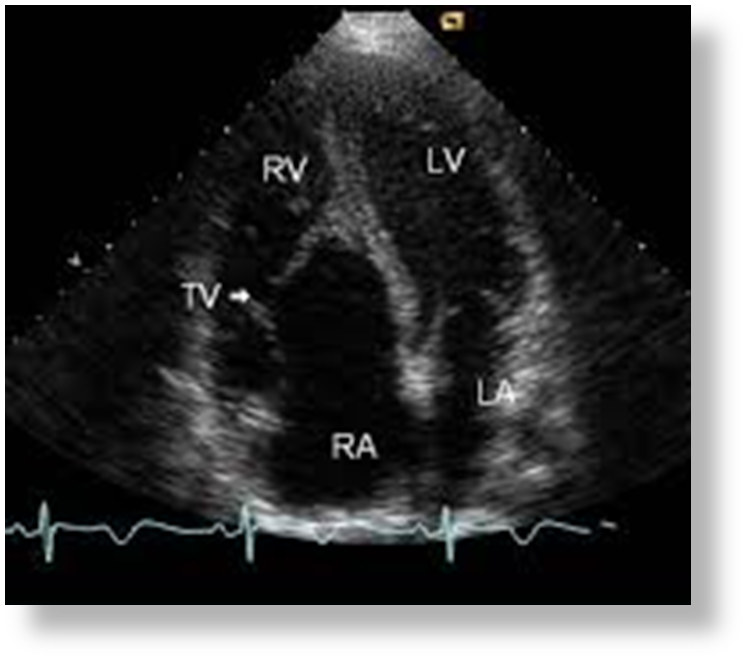

Where is the tricuspid valve located in this image?

Asses RVIT

Asses apical 4